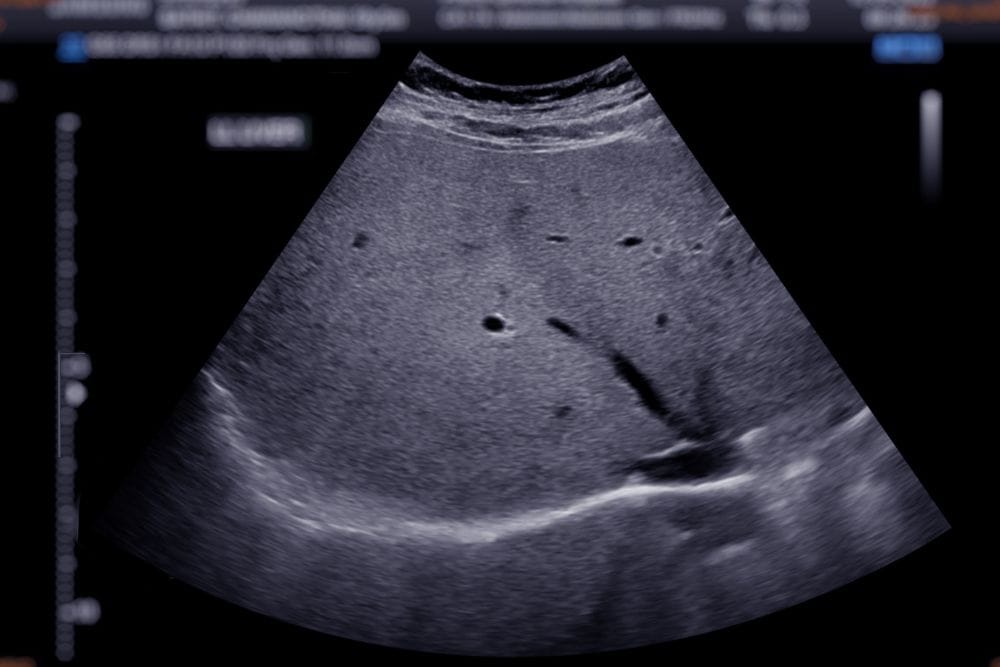

Послеоперационные серомы на узи

Послеоперационные серомы на узи 121 фотографий